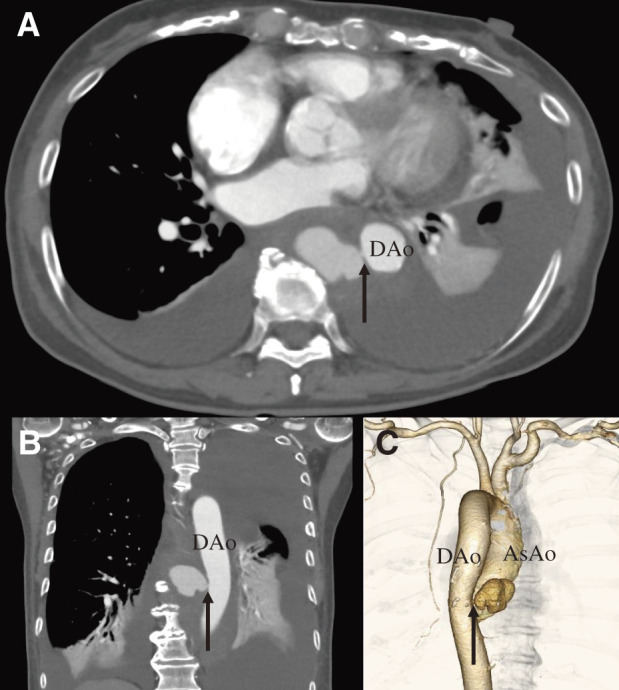

Thoracic descending aortic perforation with overlap syndrome (systemic sclerosis and dermatomyositis) is a rare, unreported vascular pathology. We describe the case of a 75-year-old woman who presented with chest tightness, back pain, and dyspnea. Computed tomography revealed a pinhole rupture in the descending aorta. The patient underwent a thoracic endovascular aortic repair and left chest drainage. Her postoperative course was uneventful.